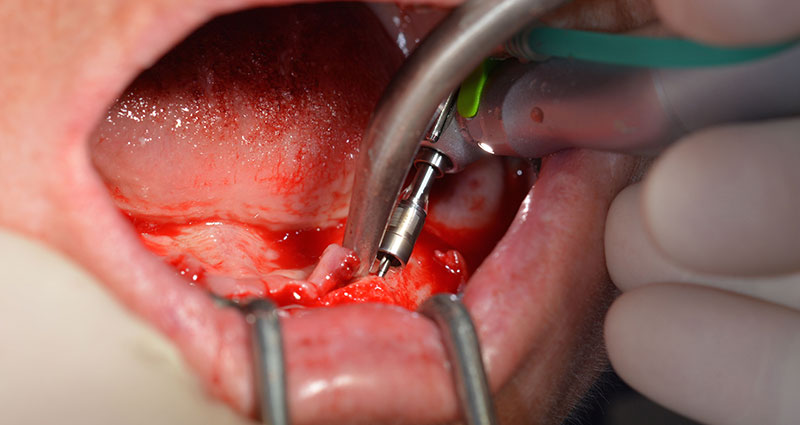

The next programmed setting is already for placement of the implants. In our practice we usually employ a torque of 32 Ncm to place the implants (Fig. 12 and 13).

W&H contra angle

Fig. 12

torque of 32 Ncm

Fig. 13

High primary stability is an absolute requirement for an immediate restoration. In order to achieve this, the hole was not tapped in this case. The W&H Implantmed drill unit used here is equipped with a suitable special mode for this, which can also be directly selected and is indispensable for many indications. The final revolutions when placing the implants exceeded the value of 32 Ncm and were performed by hand. In such cases, we recommend utilizing the implants’ self-tapping function and twisting the implants backwards and forwards several times. This allows the implant to approach the final position gradually without exerting excessive pressure on the bone (Fig. 14).

Implants

Fig. 14